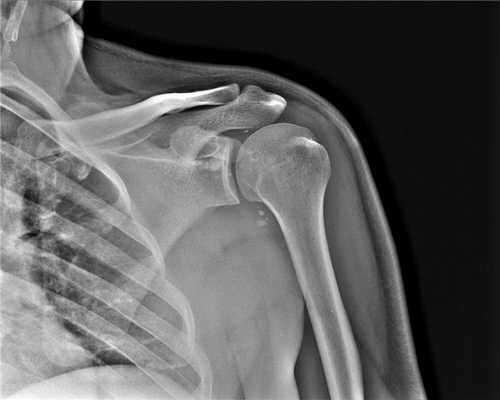

Рентгенограмма и компьютерная томограмма у пациента с тяжелым переломом и вывихом правого плечевого сустава до операции

Перелом плечевой кости

Переломы плеча составляют около 7% от общего числа переломов. В зависимости от локализации переломы плеча подразделяются на: переломы верхних отделов плечевой кости; диафизарные переломы плеча (переломы средней части плеча); переломы нижних отделов плечевой кости. Переломы плеча сопровождаются болью и отеком, деформацией и крепитацией в области перелома, ограничением движении руки. При внутрисуставных переломах плеча возможен гемартроз. Основной метод диагностики перелома плечевой кости - это рентгенография, дополнительно может проводиться УЗИ, КТ или МРТ сустава, диагностическая пункция. Лечение включает репозицию отломков, их удерживание при помощи спиц, пластин или винтов, наложение гипсовой повязки, реабилитацию руки после снятия гипса (массаж, ЛФК, физиопроцедуры).

У каждого способа обследования имеются свои преимущества и недостатки. На сегодняшний день ведущую роль в визуализации вне- и внутрисуставных структур плечевого сустава играет МРТ, которая позволяет выявлять мягкотканные и костные повреждения в суставах. Она может осуществляться по двум базовым протоколам - бесконтрастная томография и МРТ плечевого сустава с применением парамагнитных контрастных веществ (она же МР артрография). Лидирующую роль в оценке состояния костей плеча играет спиральная компьютерная томография.